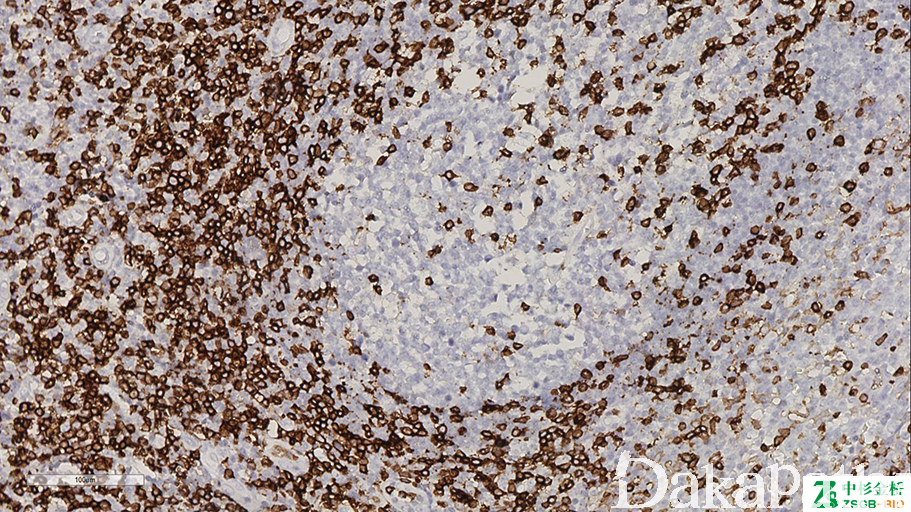

CD45RO

活化 T 细胞标志,表达于大多数胞腺细胞、T 细胞、粒细胞、成熟单核细胞以及部分巨噬细胞。

信号定位: 胞膜

- T 细胞淋巴瘤与 B 细胞淋巴瘤的鉴别。75%的 T 细胞淋巴瘤阳性,如 AITL、PTCL-NOS、皮肤 T 细胞淋巴瘤、肝/脾 T 细胞淋巴瘤等。